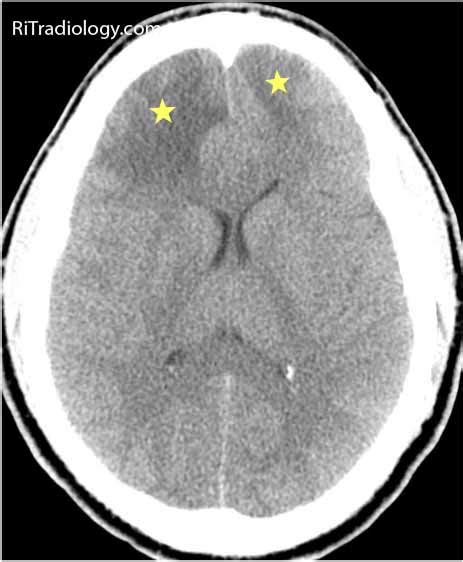

RiT radiology: June 2011

The venous circulation of the brain is done. Cerebral venous sinus thrombosis associated with oral contraceptives: Saudi j med med sci 2019;7:135‑6. Secondary sources of data included reference lists of articles reviewed and cohort studies that related treatment to outcomes. Acute symptomatic seizures in cerebral venous thrombosis. This is an open access journal, and arcles are cerebral venous thrombosis (cvt), also called cerebral venous sinus thrombosis (cvst), is a cerebrovascular disease with diverse clinical manifestations that often. This condition may also be called cerebral sinovenous thrombosis. Chronic thrombosis of cerebral venous sinuses. Cerebral venous sinus thrombosis created by paul young 22/11/07. Cerebral venous sinus thrombosis in children: Venous phase image (c) shows thrombosis of superior sagittal sinus with numerous dilated collateral venous channels. Dural sinus thrombosis (= thrombotic occlusion of one or more dural sinuses, indicated in red in a), deep cerebral venous. A blood clot in the brain may result in blood cells breaking and leaking into the brain tissues, creating a.